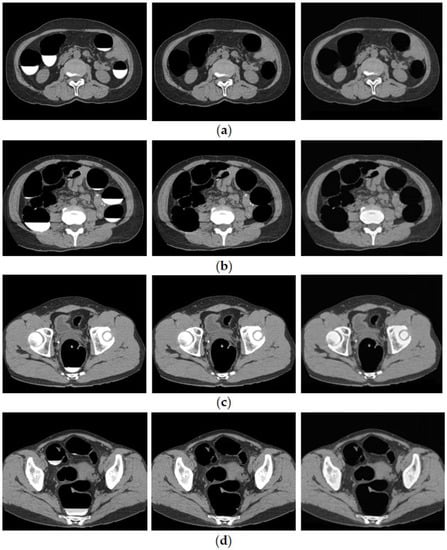

3.1. Cleansing Images Generated Using CycleGAN